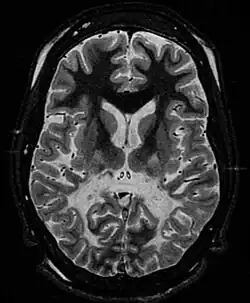

Labordiagnostisch kann eine Erhöhung der überlangkettigen Fettsäuren, v. a. von Cerotinsäure (C26:0) und den Quotienten C26:0/C24:0, C26:0/C22:0 und C24:0/C22:0 im Serum festgestellt werden. Geeignete bildgebende Verfahren, vor allem die Magnetresonanztomographie, zeigen eine symmetrische, flächige Degeneration der weißen Substanz mit Kontrastmittelaufnahme. Vorrangig betroffen sind dabei die Occipitallappen, der hintere Bereich des Corpus callosum, die Pyramiden- und die Hörbahn.[6][7]